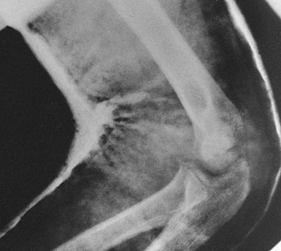

The initial radiograph often points to the degree of soft-tissue injury

and instability. In fractures of the tibia with unstable patterns,

plaster of Paris cast management alone usually results in shortening

equal to that seen on the original radiograph (Fig. 10.10).

Excessive shortening is a hallmark of more severe soft-tissue injury,

and without special measures to prevent shortening, the fracture will

heal in a shortened position. Transverse fractures with good end-to-end

contact are stable against shortening; the challenge is simply to

control angular and rotational deformity, which can usually be done

with a cast or splint (Fig. 10.11).

Figure 10.10.

The amount of shortening seen on the initial postinjury x-rays indicates the degree of soft-tissue stripping that has occurred about the fracture site. |